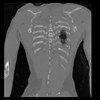

29 CUERPO,CE,Coronal,3.000,CUERPO,Coronal,